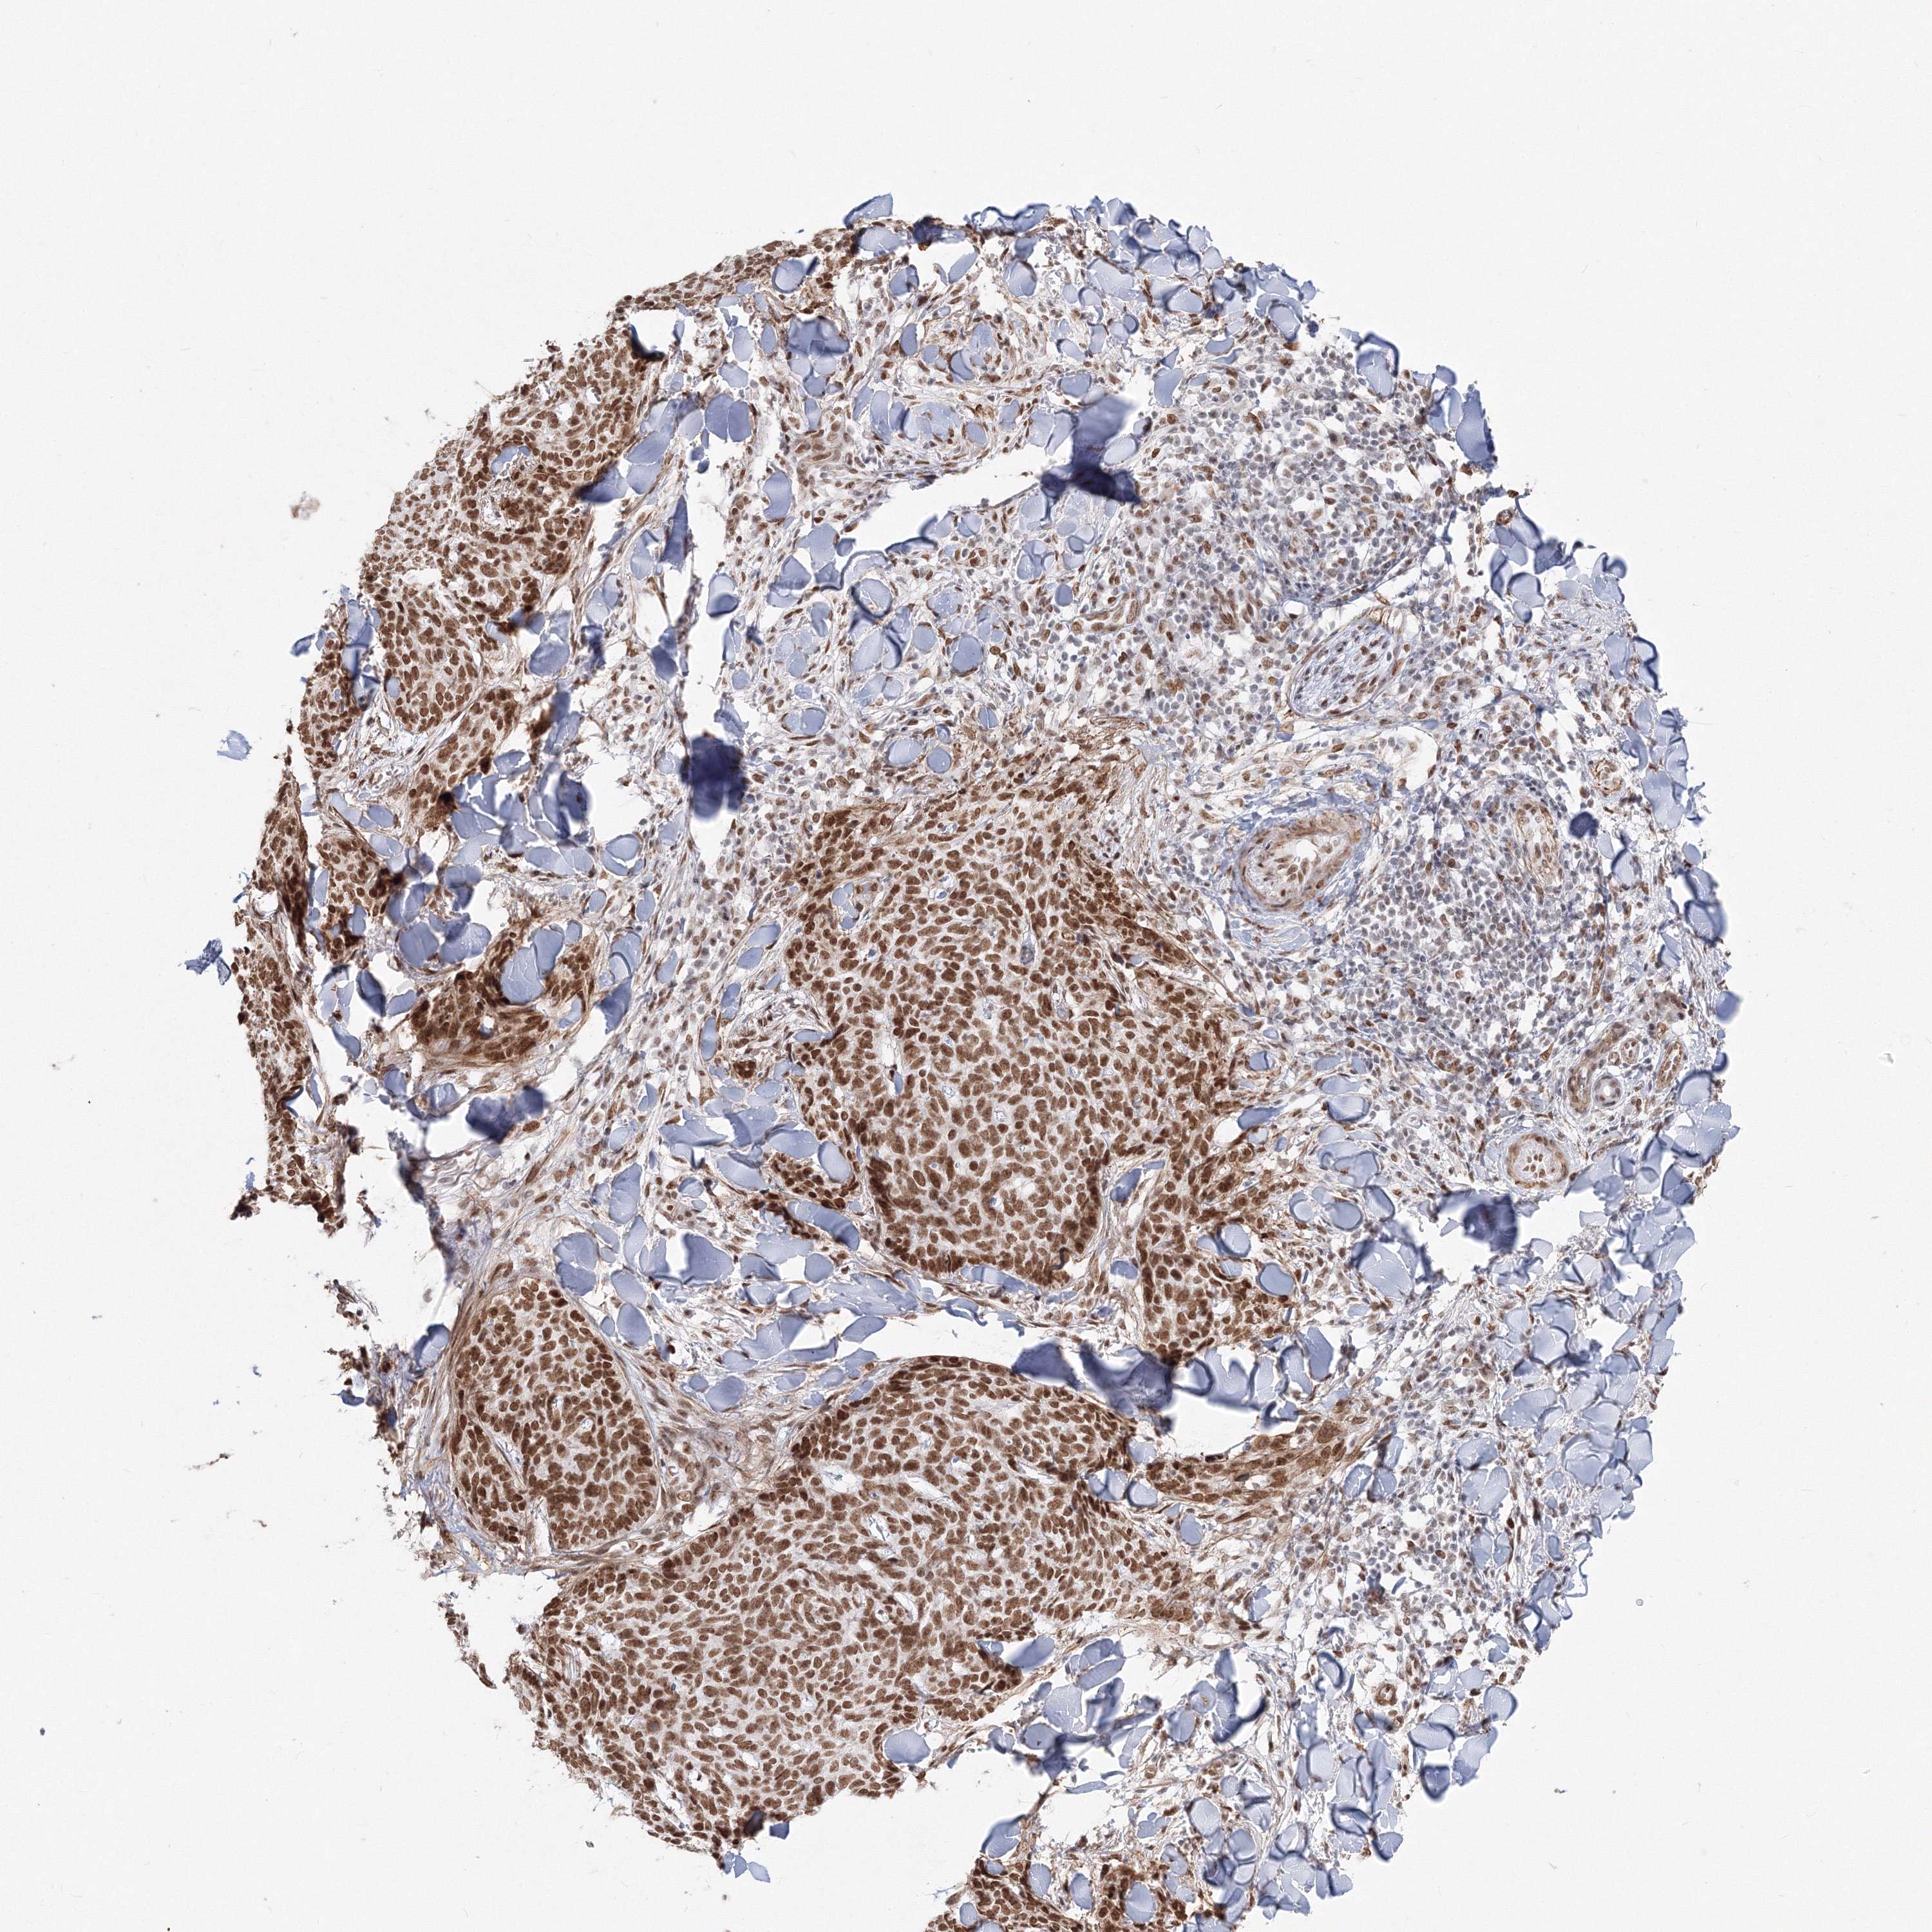

SKIN CANCER - Protein expressioni

A mouse-over function shows sample information and annotation data. Click on an image to view it in a full screen mode. Samples can be filtered based on level of antibody staining by selecting one or several of the following categories: high, medium, low and not detected. The assay and annotation is described here.

Each image is clickable and will lead to virtual microscopy that enables deeper exploration of all samples and also displays staining intensity scores, fraction scores and subcellular localization as well as patient and tissue information for each sample.

Antibody HPA036784

Staining

High

Intensity

Strong

Quantity

>75%

Location

Nuclear

Squamous cell carcinoma, NOS